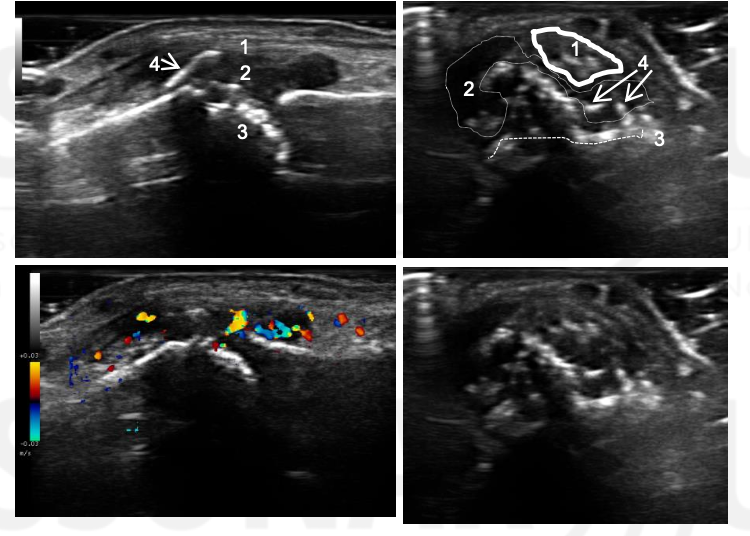

Name 1-4.

What condition is this?

IP joint of the thumb

1 - Extensor tendon

Synovitis

Proximal phalanx (eroded)

New bone formation

Psoriatic arthritis patient with swelling of the IP joint of the thumb.